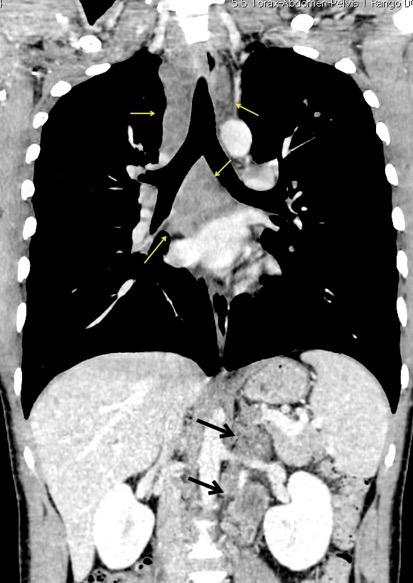

Ganglios retroperitoneales (flechas negras)

germinales del testículo izquierdo Nódulos pulmonares múltiples. (flechas verdes). Ganglios paratraqueales. (flechas amarillas). Dudoso ensanchamiento retrocrural (flechas negras)

Panda A et al. “Straddling Across Boundaries”. Thoracoabdominal Lesions: Spectrum and Pattern Approach. Curr Probl Diagn Radiol, 2015